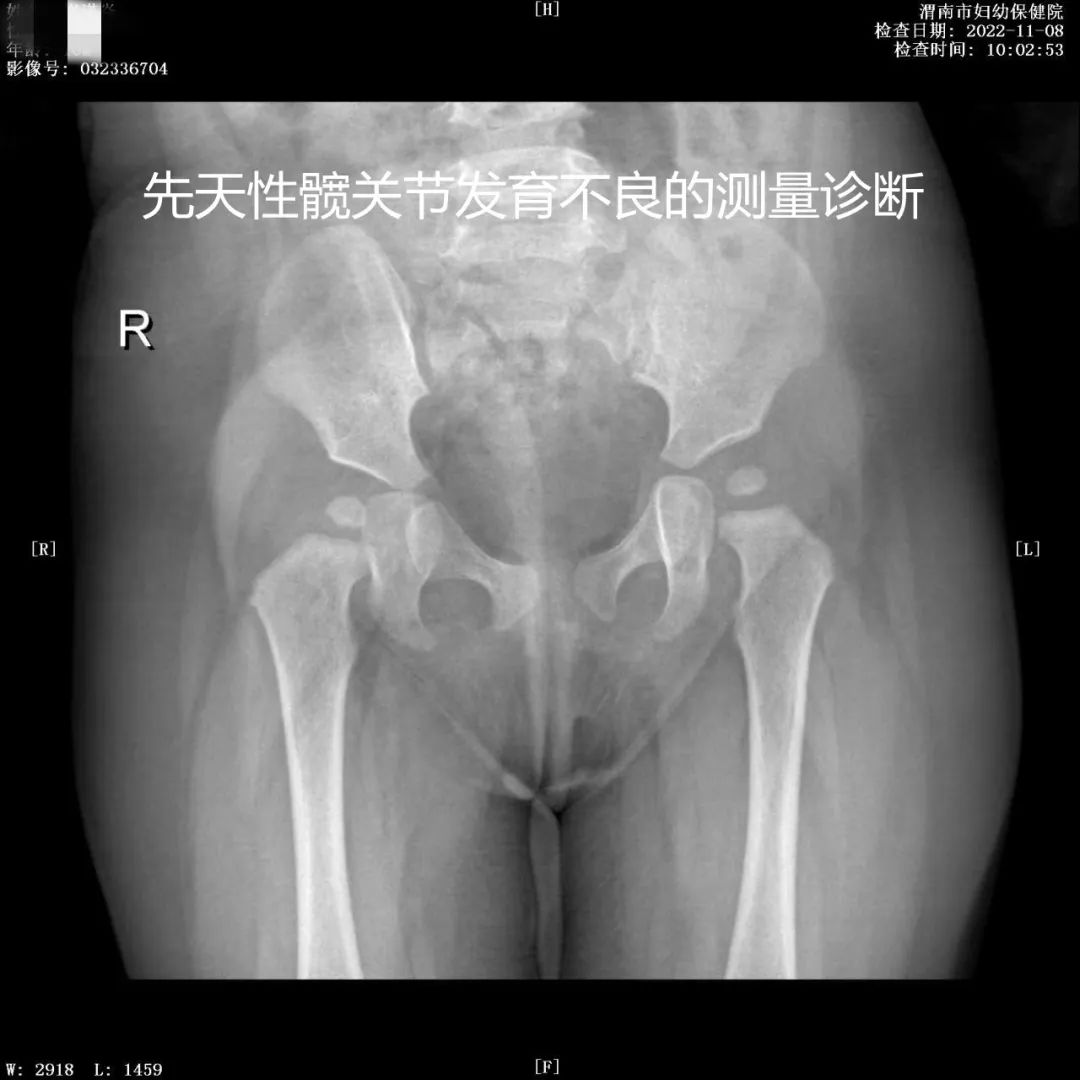

放射"摄影作品"

乳腺疾病的诊断与体检筛查